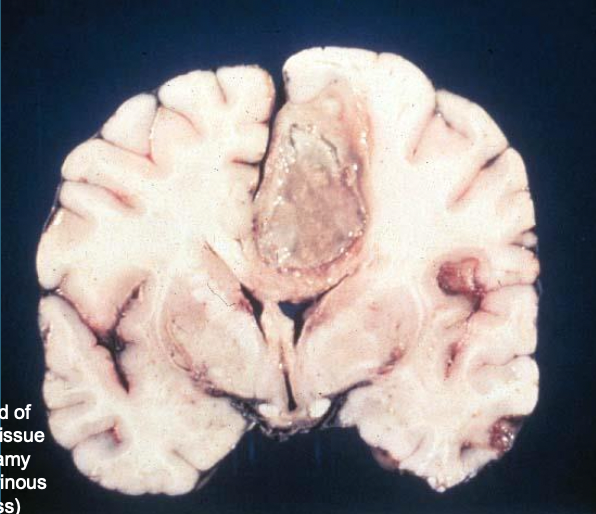

12

A

Abcesses

13

Abcess